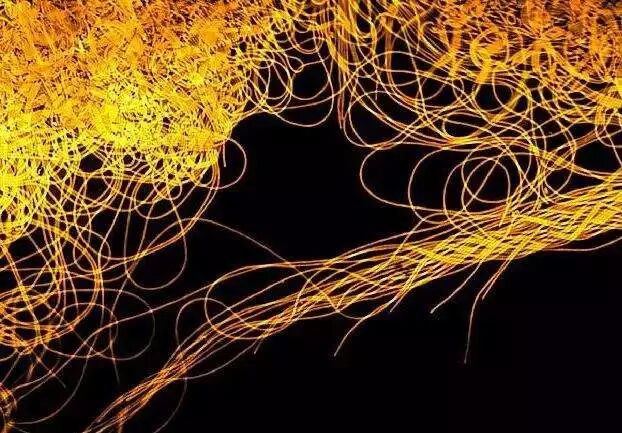

2015年10月16日,《自然》杂志又一次特别关注了肠道和大脑的关系,在一篇新闻特稿中特意用了这张魔性的图:

这脑壳里,装的像是大脑,仔细一看,居然是副大肠(还布满调皮的微生物)!是不是很魔性?

热心肠先生之前也看到过两张魔性十足的图,第一张,人肚子里长了一个“肠脑”:

第二张,调皮的微生物们正在塑造大脑:

呃(⊙o⊙)…感觉是不是很魔性?